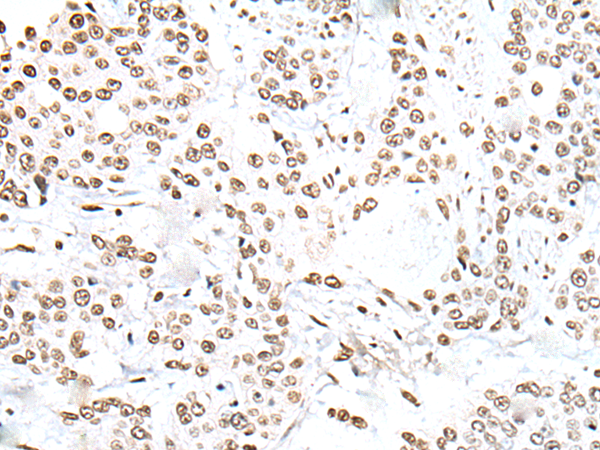

IHC positive control: |

Human lung cancer and human prostate cancer |

IHC Recommend dilution: |

25-100 |